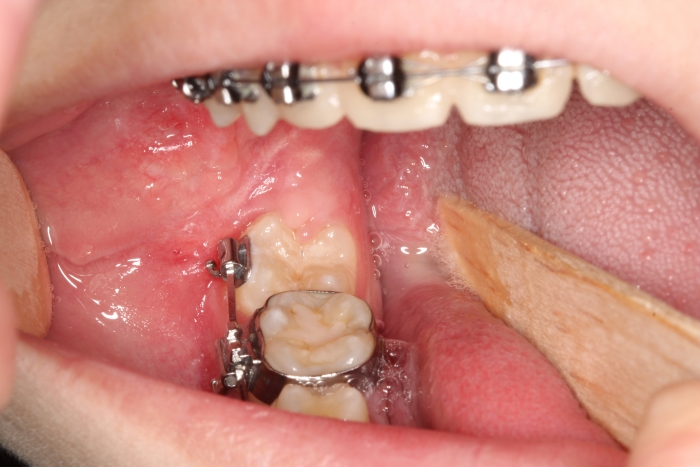

Dentes em tracionamento, imediatamente após a cirurgia - Clínica Cliniface

Dentes em tracionamento, imediatamente após a cirurgia